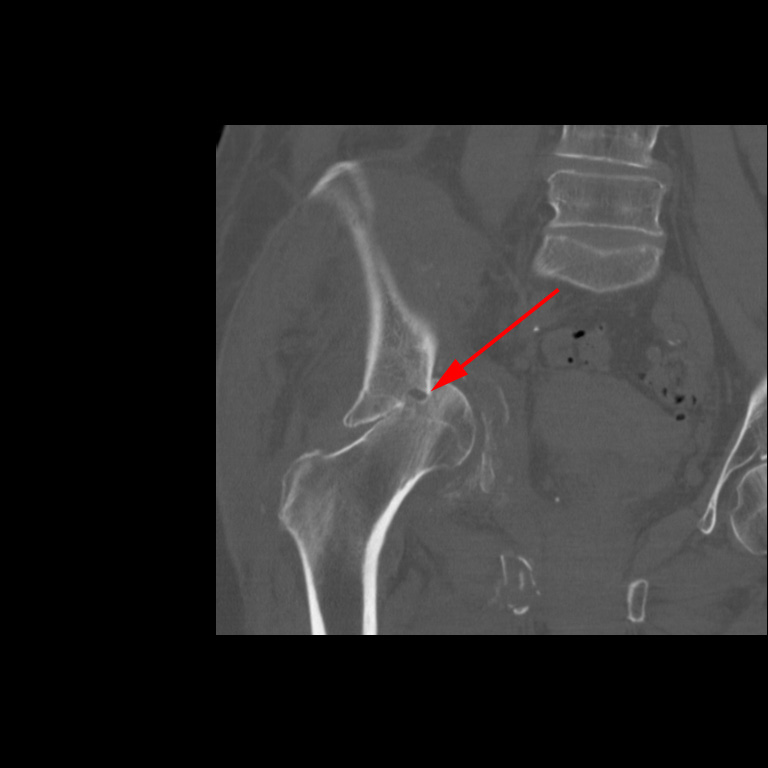

CT-skanning af højre hofte (patienten fra CT scanning ovenfor), der viser knusningen af både caput femoris og acetabulum (rød pil).